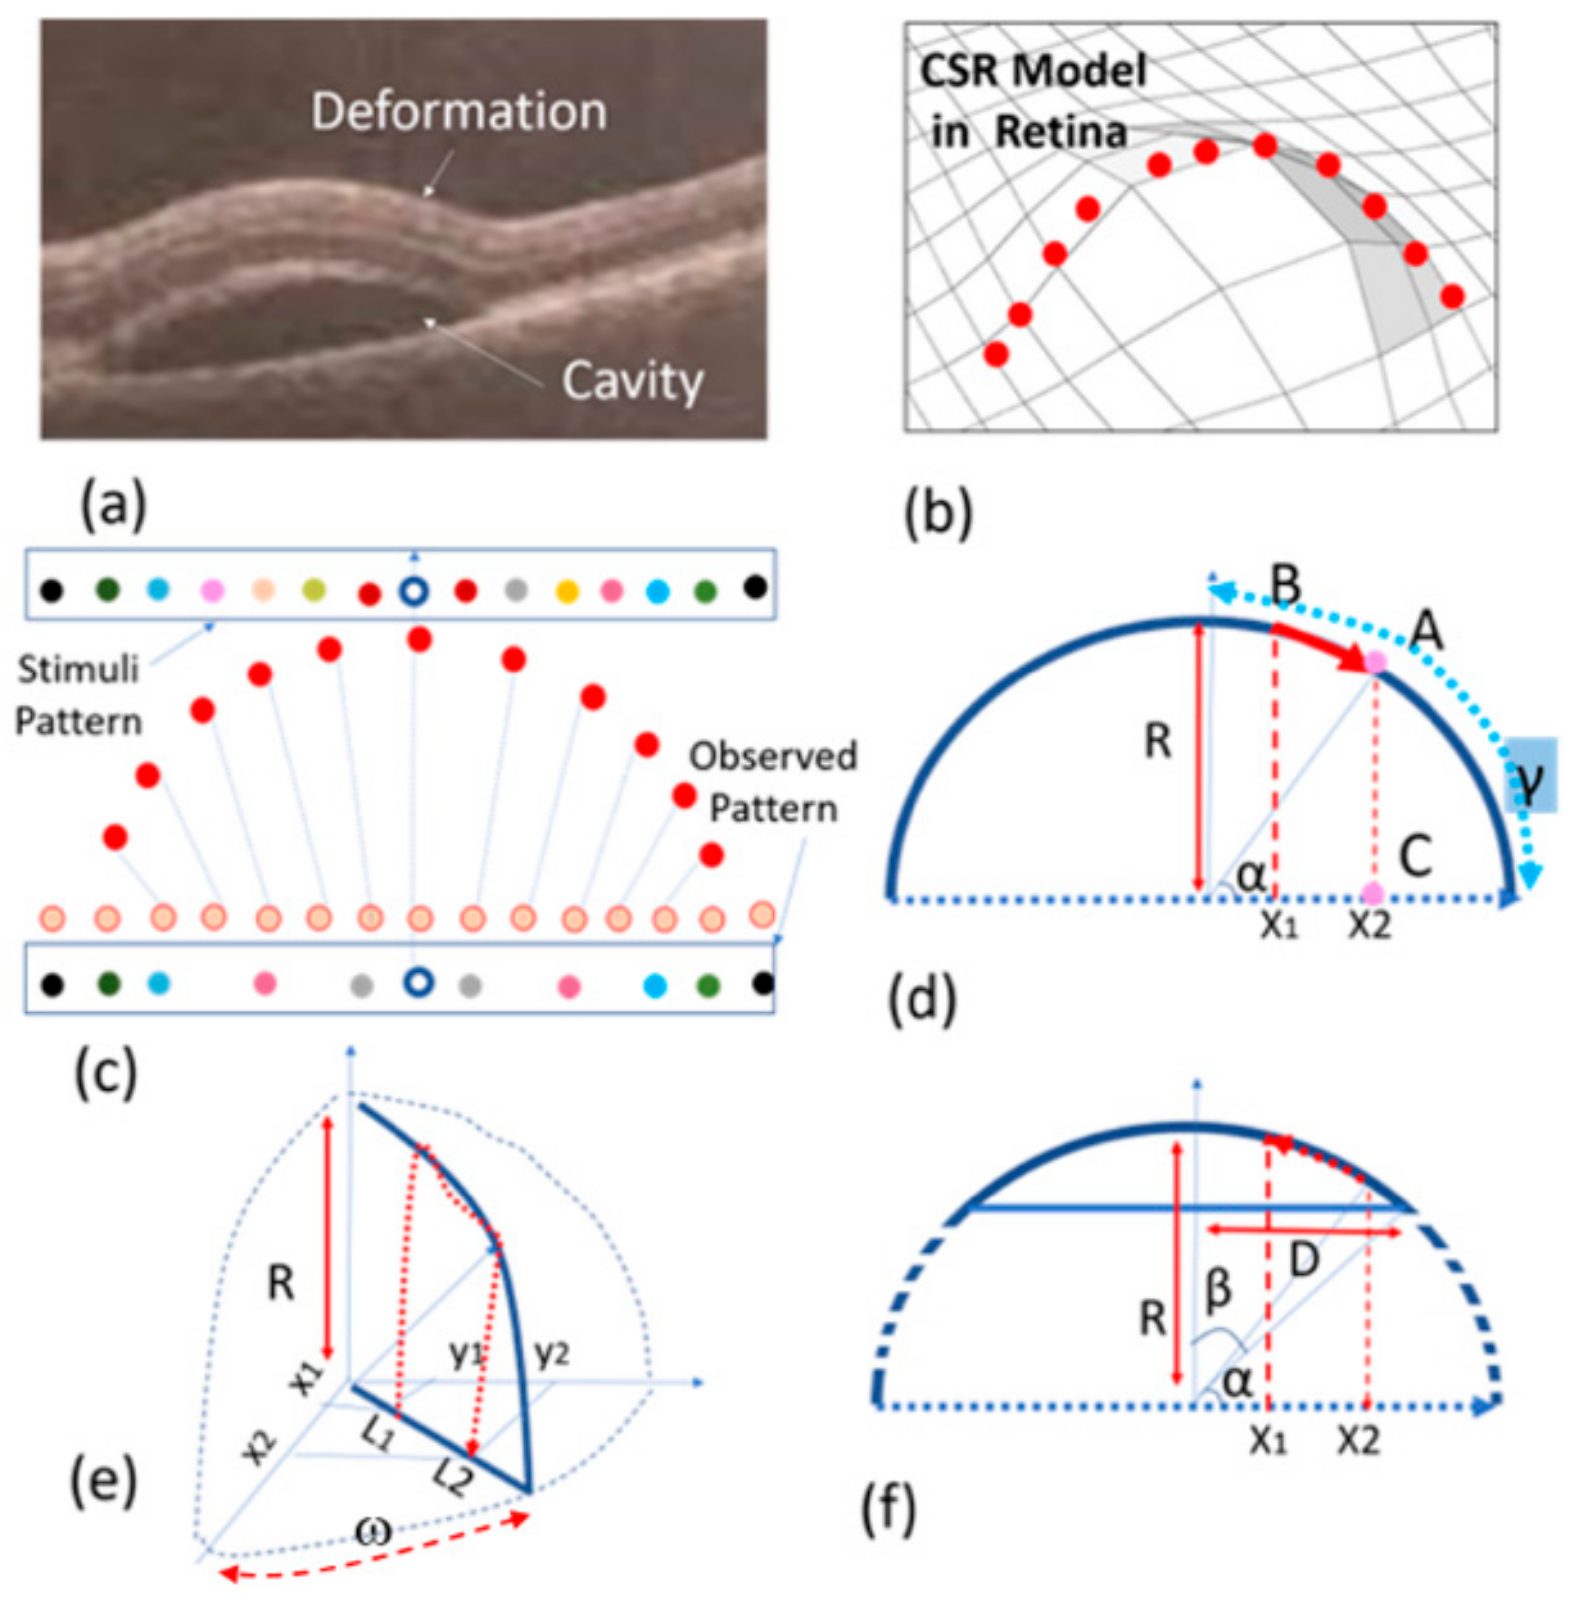

3.2. Spherical Shape CSR Modeling

5.1. Simulation Results of CSR Modeling